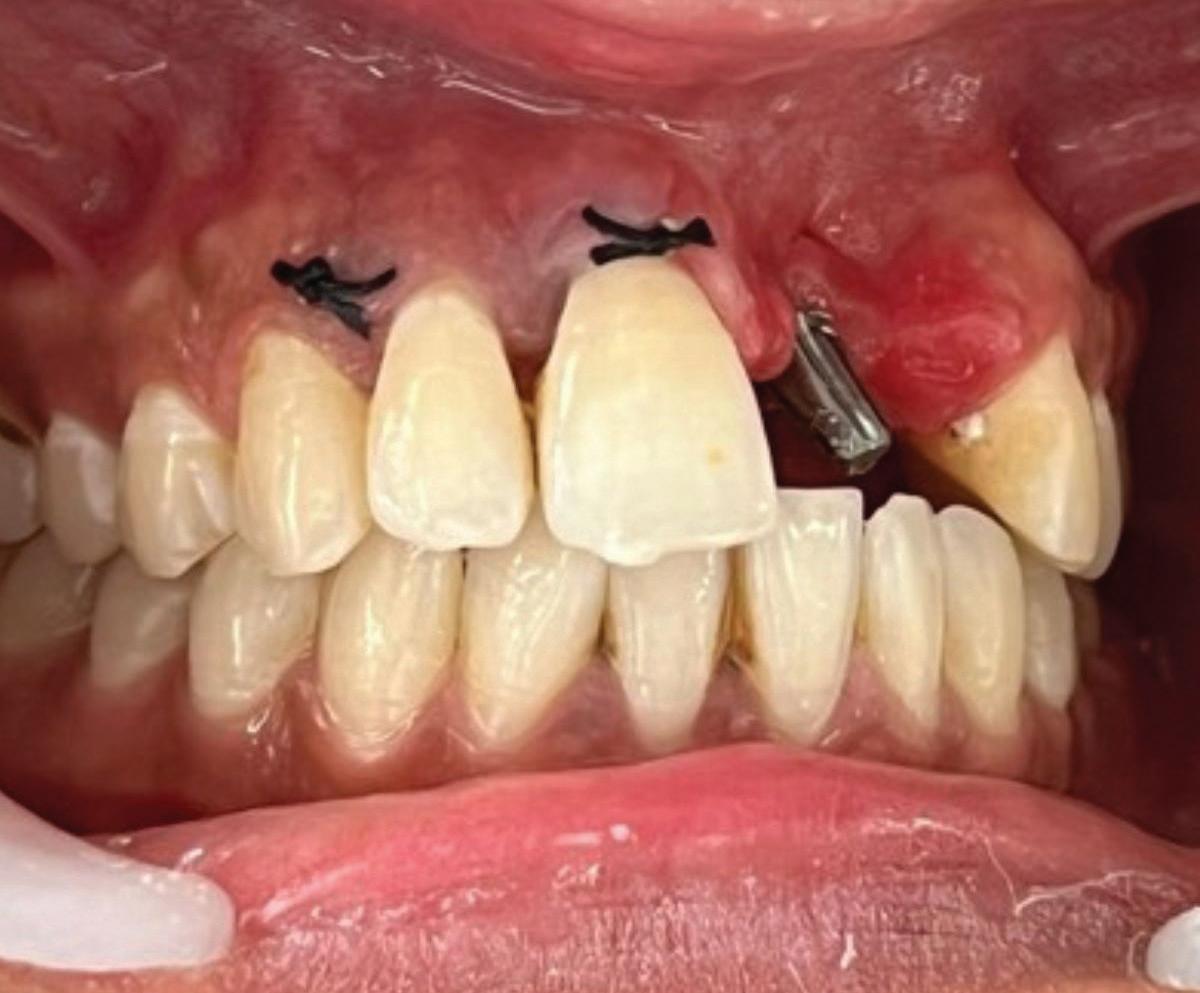

Limitations of implants as an alternative

It is increasingly important to recognize that dental implants are not an ideal tooth replacement. A growing body of literature highlights both biologic and mechanical complications associated with implants.48,49 While the prevalence of peri-implantitis is well established, recent studies have drawn attention to other concerns, particularly the loss of proximal contact due to mesial drift of natural teeth. Because implants are ankylosed, they do not adapt to this physiologic movement, often resulting in open contacts, food impaction, root caries, and localized periodontal breakdown.50

Fig 5. CBCT images of a crack-associated isolated periodontal pocketing defect associated with a distal crack in the mandibular right first molar. A. Sagittal view showing angular crestal bone loss (arrow) along a distal radicular crack at the cervical margin. B. CBCT 3-dimensional rendering showing the defect (arrow) at the distal root. C. Axial view showing the defect (arrow) at the distal root.

Emerging evidence also suggests that implants may negatively impact adjacent natural teeth. In one study, teeth located next to an implant were found to have a 13.4-fold increased risk of future tooth loss compared with those adjacent to natural teeth.51 These findings highlight the growing clinical imperative to retain natural dentition whenever possible.

While implants remain an excellent solution for restoring edentulous spaces, they are not ideal substitutes for natural teeth when those teeth are salvageable. Preserving a natural tooth, even temporarily, can offer long-term benefits. It may delay implant placement while technology and techniques continue to improve, and it may allow time for ongoing research to inform clinicians on how to better manage and mitigate implant-related complications. In this context, tooth preservation should remain a priority in modern dental practice.